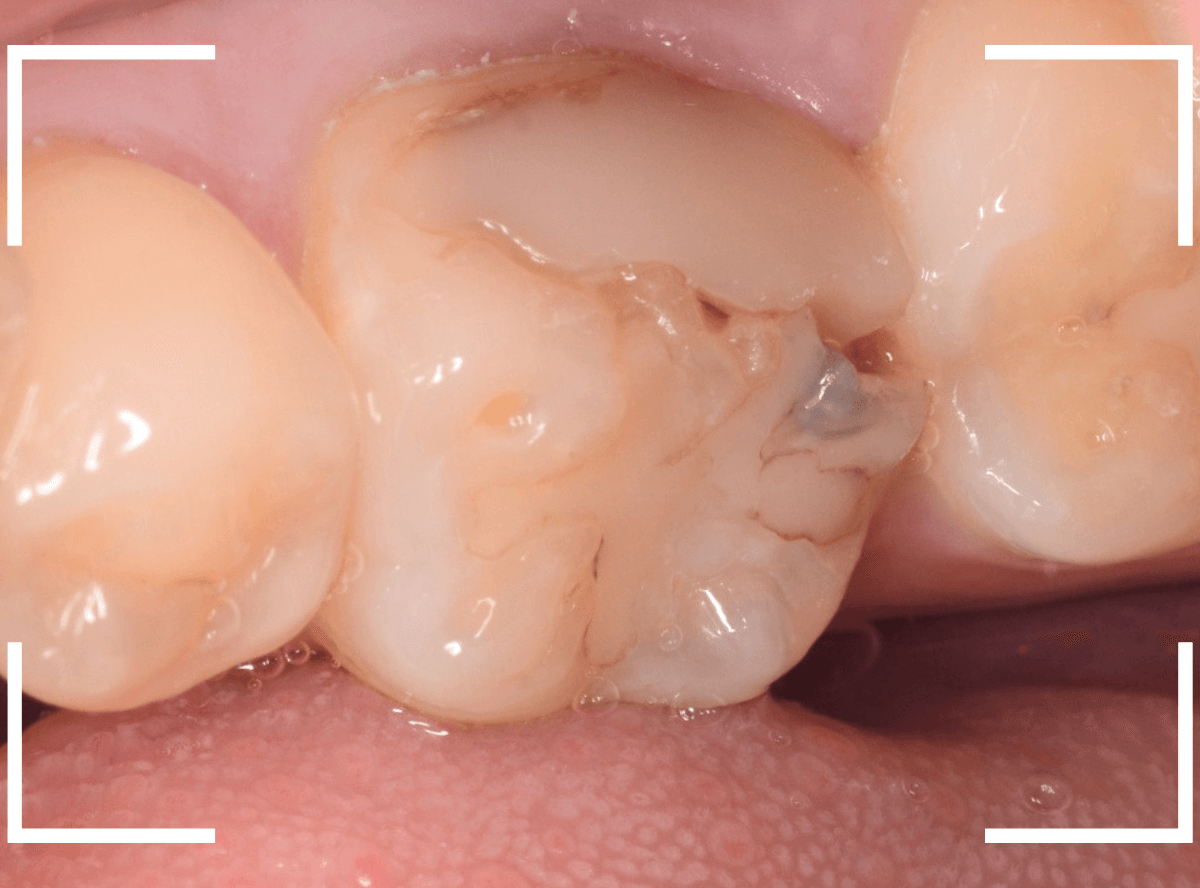

Case.11 劣化したレジンの下で虫歯

今回は、レジンの中の虫歯の話です。

以前に治療をしたレジンが劣化して変色し、中も黒くぼやっと見えます。

このような状況では、治療をすると大きな虫歯が見つかる事が多いです。

レントゲン写真で確認します。

レントゲン写真だけでは、虫歯のようには見えません。

患者さんに状況を説明し、レジンを外して中を調べると、大きな虫歯が見つかりました。